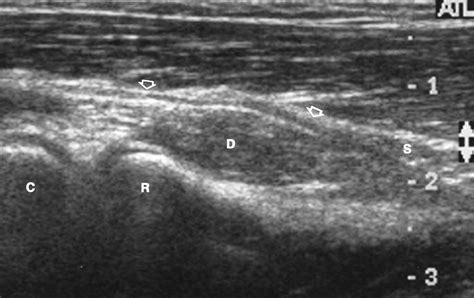

Diagnosing an injury to the Posterior Interosseous Nerve requires a careful physical examination. A doctor will typically test for weakness in finger extension, specifically checking for a "dropped finger" or the inability to lift the thumb or index finger independently. They may also use electrodiagnostic studies, such as Electromyography (EMG) or Nerve Conduction Velocity (NCV) tests, to evaluate how well the nerve is transmitting signals to the forearm muscles.